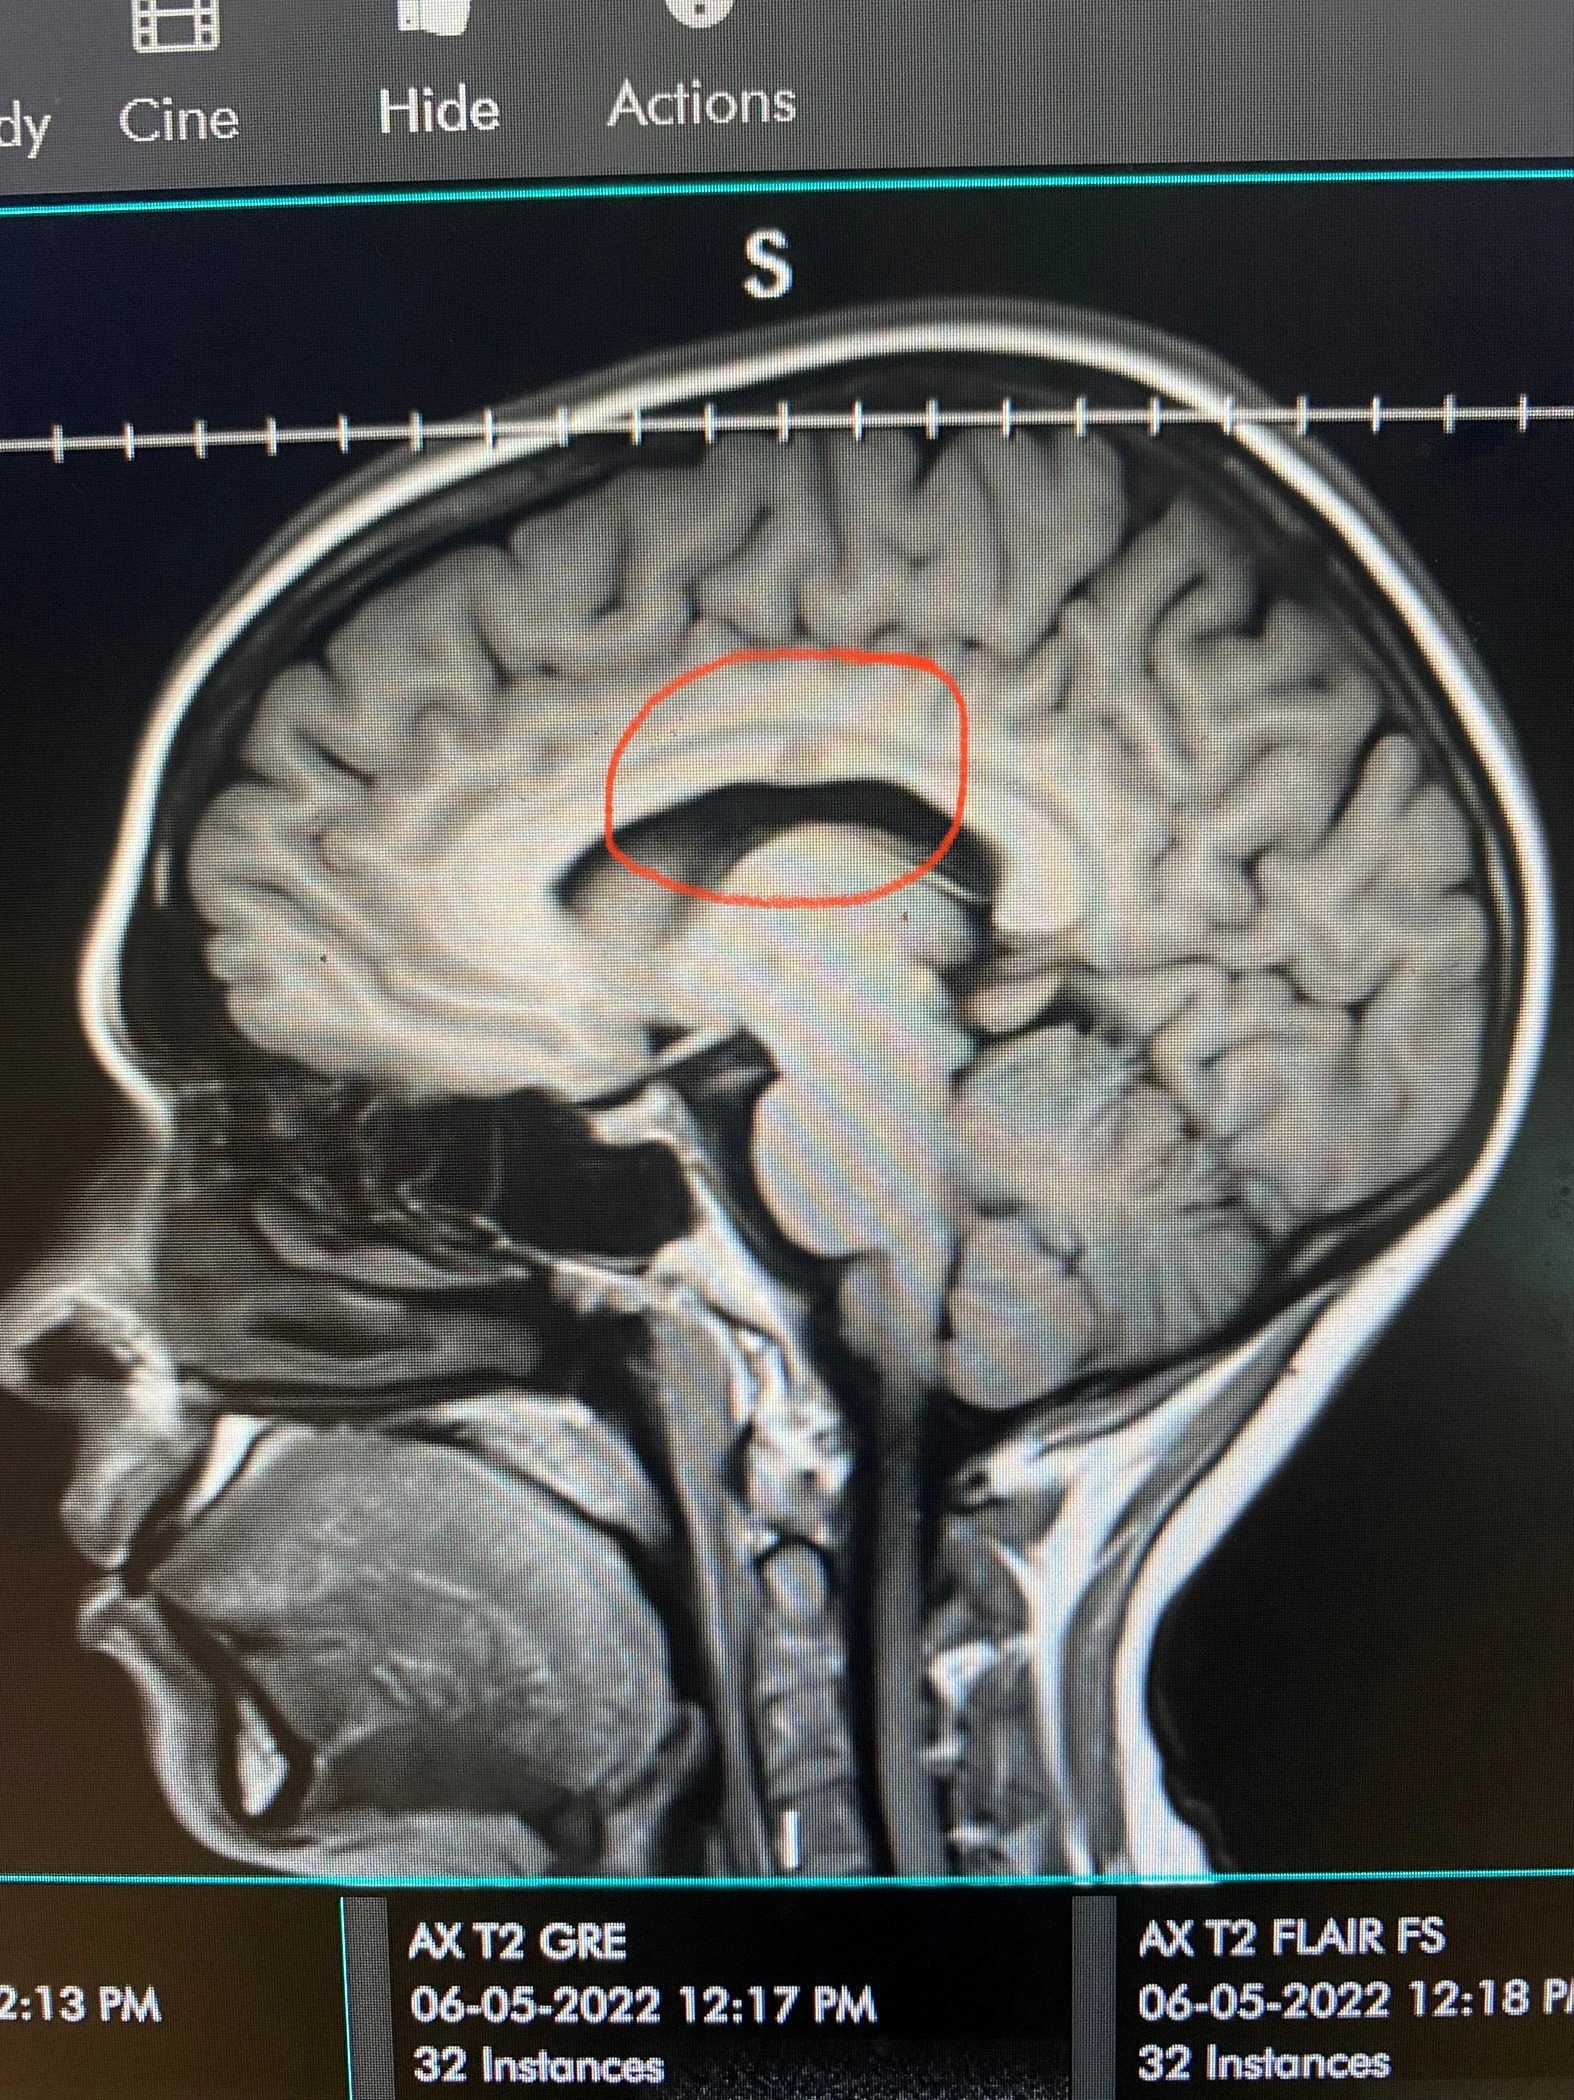

There were moments when I felt invisible in the medical system, moments where I had to advocate fiercely for myself even when I was exhausted. The process was daunting and isolating, and when I finally received my Multiple Sclerosis diagnosis, I stepped into a new kind of unknown. A diagnosis brings answers, but it also brings fear, grief, questions about the future and a sense of losing control over the life you thought you were living. There were days I felt broken, burdensome and entirely alone, even while surrounded by people who cared.